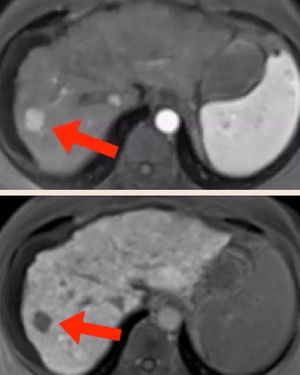

Eovist/Primovist is a gadolinium-based MR contrast agent manufactured by Bayer HealthCare designed for liver imaging. After intravenous injection the drug initially distributes into the vascular and extracellular spaces in a manner similar to other gadolinium agents. Shortly thereafter up to half of the administered dose progressively accumulates in hepatocytes and then is excreted into the biliary tract. The remainder is excreted by the kidneys through glomerular filtration. Eovist thus has double distribution and elimination pathways, allowing it to be used to assess both vascularity and function of liver lesions. Breath-hold imaging is performed with a rapid 3D T1-weighted gradient echo sequence such as LAVA, VIBE, THRIVE or CAIPIRINA using parallel imaging acceleration. At least three sets of dynamic breath-hold images are usually acquired: 1) a late arterial phase at approximately 15 seconds after contrast arrives in the abdominal aorta; 2) a portal venous phase 15-30 seconds later; and 3) a late dynamic phase 2-3 minutes thereafter. Finally, a fourth set of images in the hepatobiliary phase is acquired 15-20 minutes after injection (in patients with normal hepatic function). Hepatic enhancement generally persists for at least 2 hours following injection allowing a relatively large window for imaging. Figure: Late arterial phase (upper image) shows hypervascular metastasis in right lobe of liver (arrow). Note enhancement of aorta and spleen. Hepatocyte phase (down image) shows no uptake in this metastatic lesion (arrow).